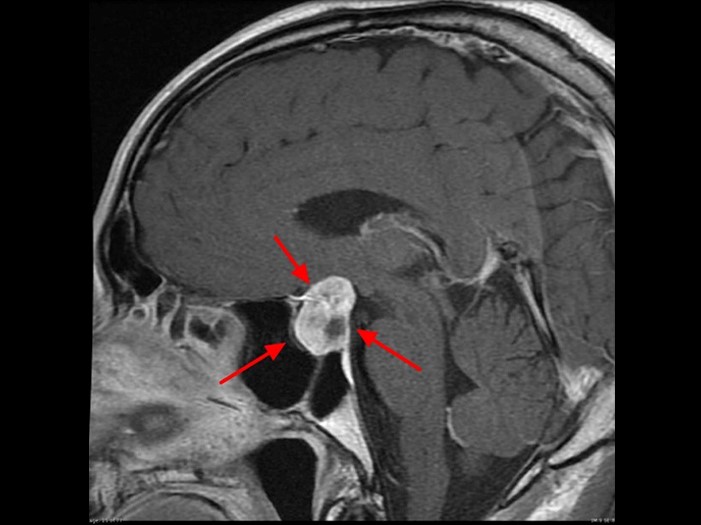

MRI(磁共振成像):MRI被认为是诊断垂体瘤的金标准,能够清晰地显示肿瘤的位置和大小,帮助医生精确定位肿瘤,并判断其是否对周围脑组织产生压迫。